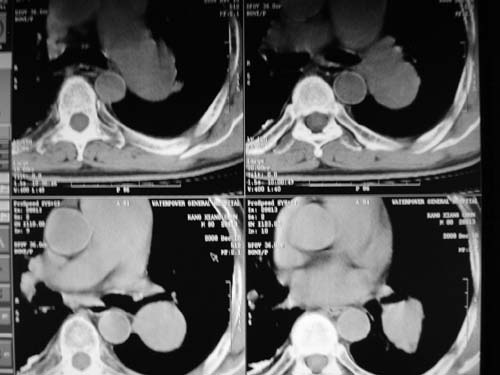

标题: CT17069:M80Y,请战友们看看像啥 [打印本页]

男,80岁

肺a高压征[左肺a狭窄?];肺,胸膜tb

右肺上叶结核;左肺门占位?建议增强扫描.

左下肺静脉扩张,原因?建议cta

左肺动脉异常增粗,建议增强。

1)考虑肺动脉狭窄。2)右肺上叶继发性肺结核。3)右侧胸膜增厚、钙化,左侧胸膜反应。

肺动脉瘤。建议先行ct增强扫描

左肺动脉异常增粗,考虑肺动脉狭窄可能。

右肺上叶继发性肺结核。

右侧胸膜增厚、钙化,左侧胸膜反应。

左肺动脉异常增粗,建议ct增强,排除肺门肿瘤

右侧胸膜增厚、钙化,左侧胸膜反应

双肺陈旧性病变,左肺动脉高压.

1)考虑左肺动脉瘤可能性大,建议增强。2)右肺上叶继发性肺结核。3)右侧胸膜增厚、钙化,左侧胸膜反应。

肺动脉段突出,左右肺门不等大,左肺门明显增大,肺动脉干及左肺动脉明显增宽,考虑先天性肺动脉狭窄瓣膜狭窄型。

)考虑肺动脉扩张,右心室增大,主动脉弓段正常位弓后段明显变小(不会是动脉导客未闭吧,不知患者有何症状病史)0。2)右肺上叶继发性肺结核。3)右侧胸膜增厚、钙化,左侧胸膜反应。

右肺上叶尖段结核;左肺下叶占位?建议增强扫描。右侧胸膜增厚;右肺局限性肺气肿。

结合患者年龄,不除外左下肺扩张性动脉瘤,建议胸透是否有扩张性博动,以便确诊。

肺动脉高压,左肺动脉瘤样扩张。